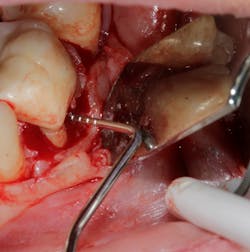

No. 2—The anatomy of the roots in the furcation are often concave and very hard to instrument, even if access to the furcation is possible (figure 4).

Technology solution: Many commercially available lasers have handpieces with tips capable of side firing and/or radial firing. This would be similar to an umbrella opening up or being in a cave and having the ability of a flashlight to completely illuminate in a 360-degree direction. In other words, the laser has the capability to penetrate all areas and convexities harboring the bacteria that is preventing proper detoxification/tissue regeneration.